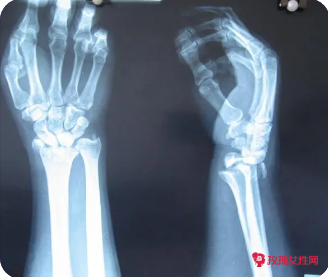

骨折用牵引的作用

腿骨折做牵引是可以进行转院治疗的,可以到正规的医院进行治疗。腿部骨折可以服用接骨类的药物,促进骨痂的愈合,具体用药谨遵医嘱,骨折之后不要过早的进行运动,以免出现后遗症,一般三个月左右可以在专业的康复师指导下进行拄拐杖走路训练。

骨折牵引是什么

皮肤牵引主要适用于四肢长管状骨骨折,因为皮肤牵引力量较小,不适合长期牵引。还有另一种临床情况,如股骨干骨折,需要皮肤牵引。手术前皮肤牵引的目的是放松骨折周围的肌肉,为手术做准备。皮肤牵引时,应定期复查x光片,观察骨折部位,随时调整牵引重量,使骨折部位达到预期效果。

骨折牵引术的作用

如果患者大腿骨折,且骨折端有较大的缩短、旋转和角度,可采用牵引进行治疗。如果患者患有远端股骨干骨折,可以使用骨牵引。牵引安装后,定期观察骨折部位是否理想。如果位置不理想,可通过调整牵引重量来调整位置。同时,应在股骨干上安装石膏支架或支柱进行固定。如果股骨干位置不理想,可以考虑手术治疗。

骨折牵引的作用和目的.

首先,当牵引时要保持自己在正确的牵引位置,股骨颈骨折和股骨粗隆间骨折牵引时,患肢需要保持中立的外展位,患肢应尽可能在股骨上段骨折时进行牵引。其次,牵引重量应根据病情的需要进行调整,不能随意增加或减少,牵引重量过小,不利于骨折复位和畸形矫正。

骨折用牵引的作用是什么

患者属于骨折,骨折牵引是为了骨质之间生长,如果不牵引,是有可能出现骨质之间已经“过界”的,现在可以采取复位,在复位后可以采取石膏固定,口服活血化淤、止疼药物,一定要抬高患肢,要注意休息,不可以过于劳累,不可以负重,以免不利于恢复。